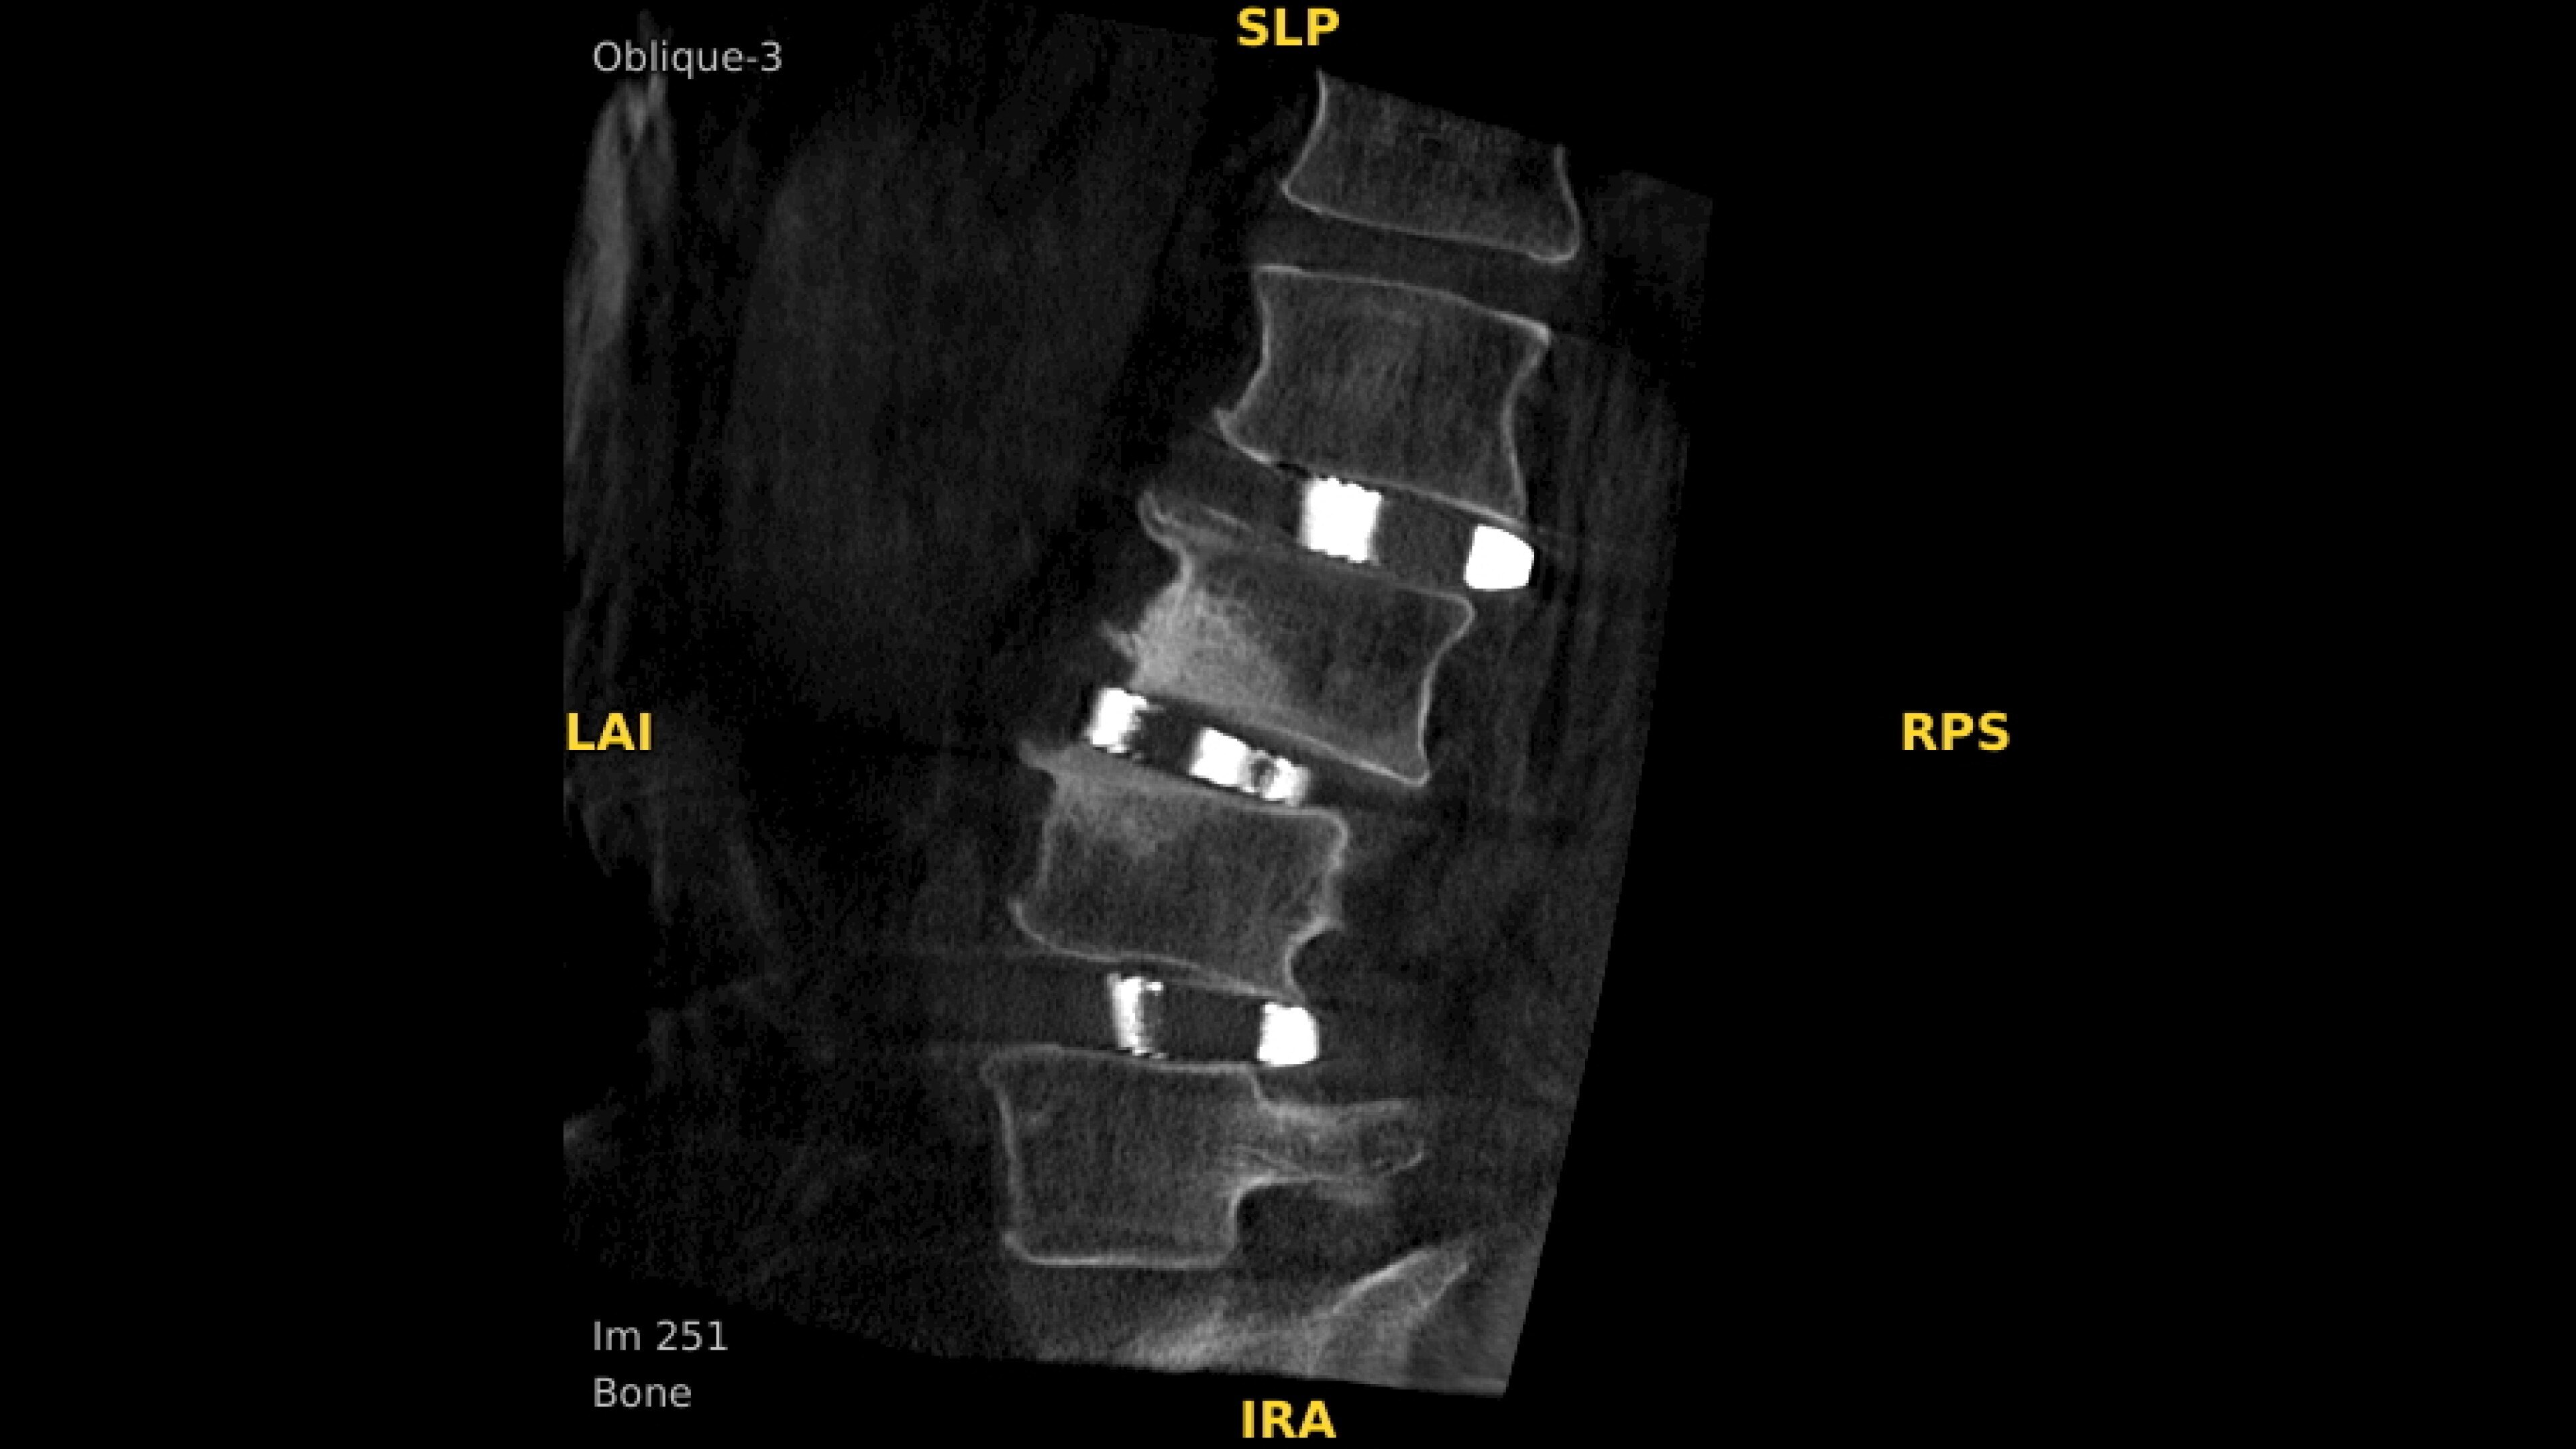

Precise analysis

Enhance intraoperative decision-making with visualization capabilities of Augmented Fluoroscopy in the OEC 3D Volume Viewer. Analyze five perspectives with 3D imaging tools including Multi-Oblique Mode, scrolling 512 slices, zoom, and more.